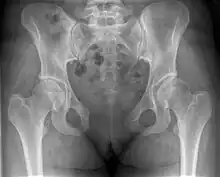

| Post traumatic pubic symphysis diastasis | |

This abnormally wide gap can be diagnosed by radiologic studies such as X-ray, Ultrasound, MRI, CT scan or bone scan. While X-Ray is the gold standard to identify a separation of the pubic symphysis, a decision must be made in regard to which imaging modality to utilize that is patient and case-specific.[3]

X-ray

An X-ray film obtained in the AP view of the pelvic inlet and outlet will show a marked gap between the pubic bones.[3] A normal pelvis will show a gap that is 4–5 mm. However, in pregnancy the hormonal influences cause relaxation of the connecting ligaments and the bones separate up to 9 mm. A gap measuring greater than 10 mm indicates a pathological process.[3]

In addition, a view in the "flamingo stance" can be obtained to demonstrate the instability of the joint. This position consists of the patient standing with weight on one leg and the other bent.[6] A vertical displacement of more than 1 cm is an indicator of symphysis pubis instability.[7] A displacement of more than 2 cm usually indicates involvement of the sacroiliac joints.[3]